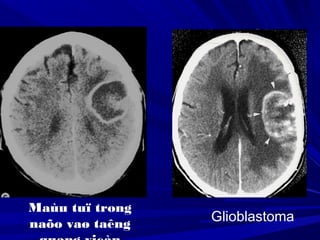

Glioblastoma

Maùu tuï trong

naõo vaø taêng

Ñoaøn thò S., Nöõ, 80 tuoåi, Xuaát huyeát khoang

döôùi nheän